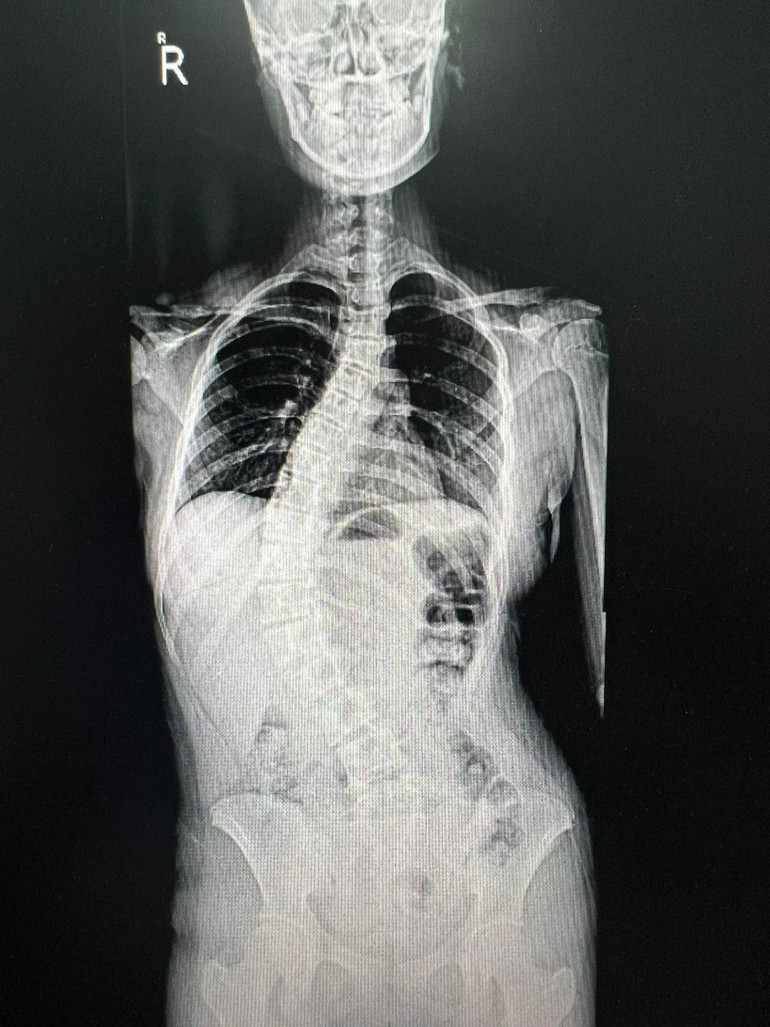

![]() |

| Hình ảnh gù vẹo cột sống ở trẻ em |